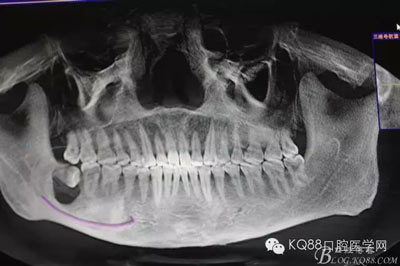

圖3.這張重建的全景片,似乎48就漂浮在囊腔上方,由此感覺48拔除如同探囊取物一般。